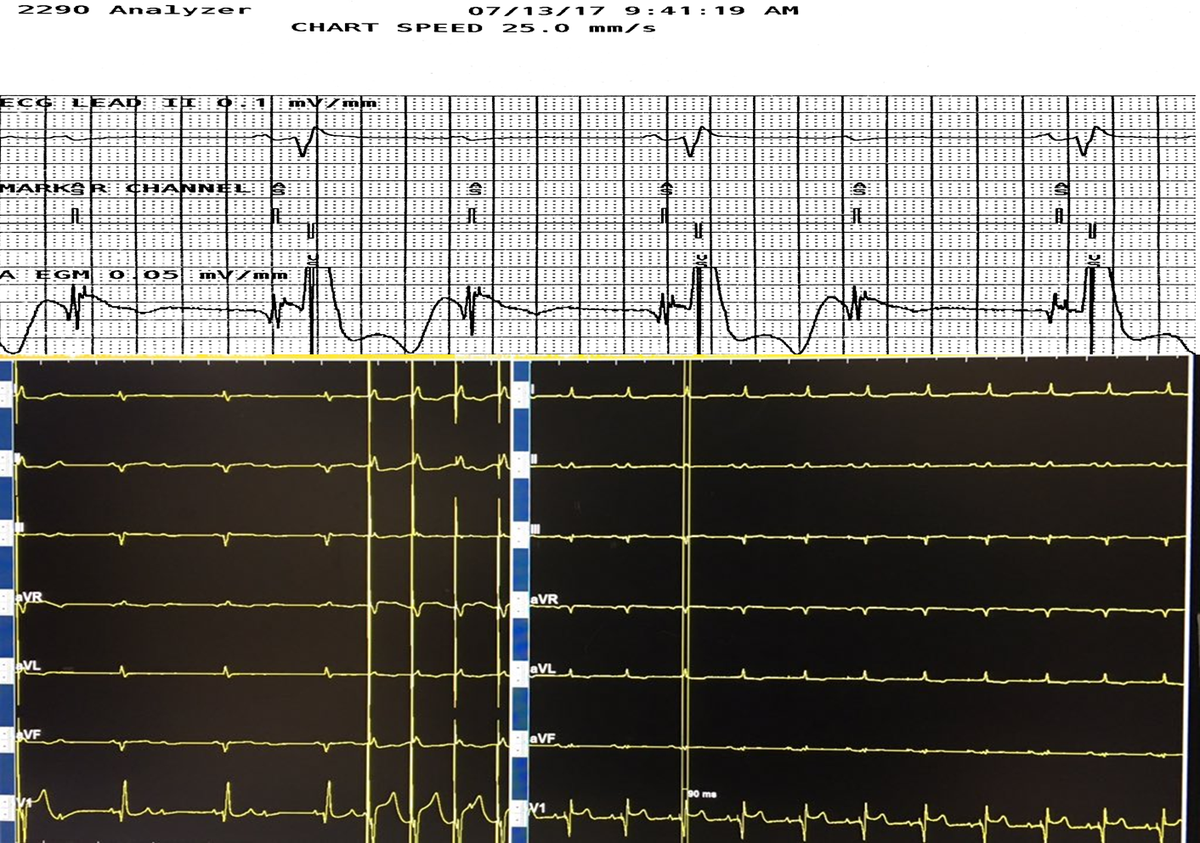

65 yo with symptomatic multifocal PVCs, ~30K, EF 45%,  3 different PVCs were ablated today..fun & require patience, thanks to the team!